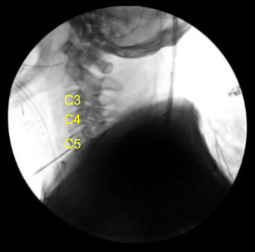

A transverse incision on the right side of the neck was planned, centered over C4 vertebra. C-arm was used to localize the level. A transverse incision of about 5 cm was given over the right side of the neck. Hemostasis was achieved.

Disc space was localized and marked with the spinal needle. C-arm was used to locate the level and found to be C4-5. The C-arm was removed and the disc space was marked with the Bovie for localization. Now, midline dissection was performed by raising the longus colli on either side from the lower C3 to the upper C6.